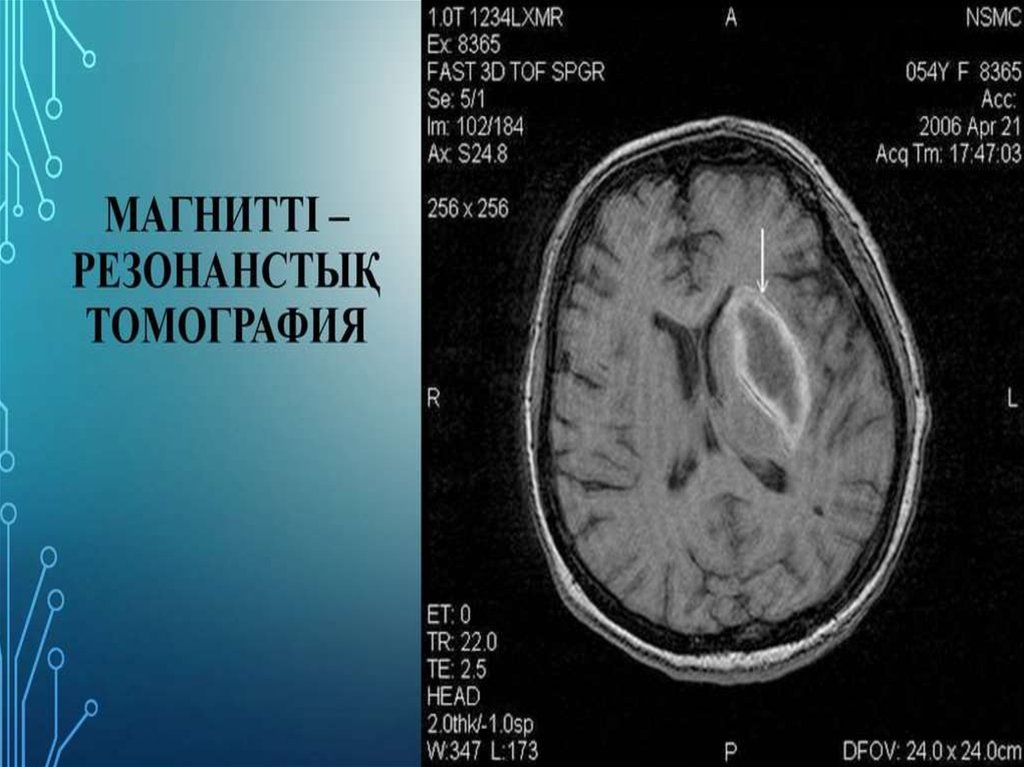

Зерттеу тәсілдері